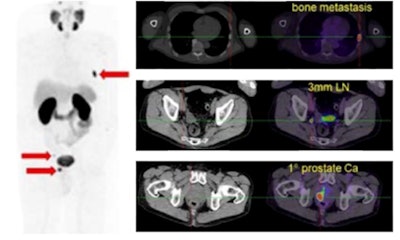

Gallium-68 (Ga-68)-labeled prostate-specific membrane antigen ligand PET/CT in prostate cancer.

Gallium-68 (Ga-68)-labeled prostate-specific membrane antigen ligand PET/CT in prostate cancer.The new document supersedes the previous "Evidence-Based Indications for the Use of PET-CT in the United Kingdom" guidelines published by the Royal College of Radiologists (RCR) in 2016. The document will be updated at regular intervals.